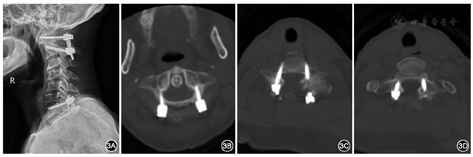

女性,66岁,因"行走不稳7年,双下肢麻木无力加重1周"于2018年6月8日入院。患者7年前无明显诱因出现行走不稳,转身困难;1周前出现双下肢麻木、无力,不能行走,双上肢无明显症状,无明显排便、排尿困难或大小便失禁,无鞍区麻木、晨僵,无关节红肿、发热畏寒等,否认既往头颈部外伤史。患者症状持续不缓解,遂于我院就诊。体检:右侧肋弓以下痛觉减退,左侧胸骨角平面以下痛触觉减退,双下肢位置觉消失,会阴部痛触觉减退不明显,两侧上肢肩外展、屈伸肘、伸腕、握拳及小指外展肌力均为Ⅴ级,两下肢屈髋、伸膝、足背伸、踇背伸及跖屈肌力Ⅱ级,双上肢肌张力无明显增高或降低,两下肢肌张力稍增高,双侧肱二头肌腱反射(++),双侧肱三头肌腱反射(++),双侧膝腱反射(+++),肛门反射(+),双侧Hoffmann征阴性,双侧Babinski征阳性。脊柱MRI检查结果示:颈椎生理曲度反弓,颈椎退行性改变,寰齿关节前间隙增宽,寰枢椎脱位,压迫相应颈髓;C7椎体向前滑移;C6~T1水平黄韧带区域占位性病变,呈T1WI低信号、T2WI高信号,考虑囊肿,椎管狭窄,相应颈髓受压、信号增高(图1)。脊柱CT平扫示:占位性病变内可见散在点状钙化。颈椎动力位X线片示:寰枢椎明显不稳。过伸位X线片示:寰枢椎脱位可复位(图2)。实验室检查:类风湿因子、抗溶血链球菌O、免疫球蛋白(IgG、IgM、IgA)、补体C3及C4、抗核抗体、抗中性粒细胞胞质抗体均呈阴性,血尿酸未见明显异常。诊断:(1)退行性寰枢椎脱位(可复性);(2)C6~T1水平椎管内硬膜外占位:黄韧带囊肿?(3)C7椎体滑移Ⅰ度;(4)不完全截瘫。因患者同时存在退行性寰枢椎脱位与C6~T1水平椎管内占位,均对颈脊髓造成明显压迫,考虑患者不完全截瘫由C6~T1水平椎管内占位所致可能性较大,但不能完全排除寰枢椎脱位影响,故于2018年6月19日在全身麻醉下行"颈后路寰枢椎脱位切开复位,椎弓根螺钉内固定术"及"颈后路C6~T1水平椎板切除及椎管减压,椎管内硬膜外占位切除,椎弓根螺钉内固定术"。术中在切除病变水平椎板后发现此处黄韧带增厚明显,可见囊肿样病变组织位于黄韧带内,被黄韧带包裹,压迫脊髓,椎管明显狭窄,病变与邻近小关节间无接触及交通。术中小心地从硬膜外剥离并完整切除病变组织及周围黄韧带,此过程中增厚的黄韧带与硬膜囊无明显粘连。体外切开病变组织见其内含凝胶样黏液,囊壁与黄韧带粘连紧密,较难分离,提示病变组织起源自黄韧带。术后复查X线片及CT可见颈椎内固定稳固,寰枢椎脱位已复位,C6~T1水平椎管减压充分(图3)。术后病理学检查示:镜下见纤维组织增生,胶原变性,部分区呈囊壁样结构,散在钙盐沉浸,并见少量软骨组织,未见滑膜层,未见异型细胞、尿酸盐沉积。病理学诊断为黄韧带囊肿(图4)。术后2周患者可在搀扶下站立;术后3个月可在搀扶下行走,但步态不稳,双下肢麻木较前有所好转;术后6个月可独自拄支具行走,但双下肢仍有麻木感,较术后3个月时无明显好转;术后9个月随访时患者可独立行走,步态仍不稳,双下肢麻木较前无进一步改善。术后未见明显并发症,患者及家属对治疗过程满意。